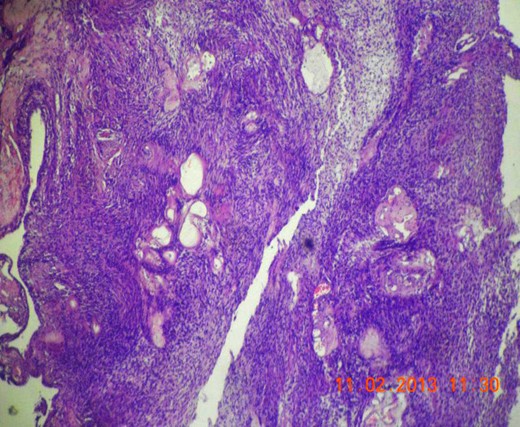

Gross appearance showed 6 × 4 × 4 cm smooth encapsulated right thyroid swelling with a posterior cystic area which was yellowish brown in colour. Walls of the cyst were bright yellow with polypoid areas (Fig. 4). Histology showed classical Antoni A (hypercellular areas) with Verocay bodies and Antoni B (hypocellular) pattern, with interspersed thyroid cells along the periphery (Figs 5–7). The lesion was reported to be arising from within the thyroid gland itself and not extrinsic to it.

Microscopic section (H&E slide, 40×) of Verocay bodies within Antoni A pattern.